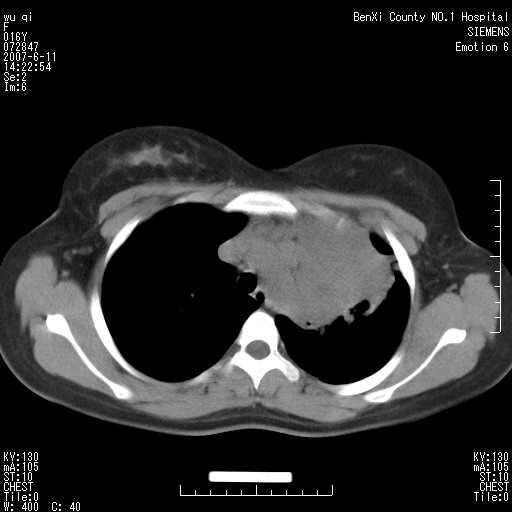

女.16、咳嗽、乏力、消受,食欲差,一个月余,无咯血,一个月前有发热。经抗炎治疗发热消失,仍咳嗽。平扫ct值34-45hu,增强后60-78hu明显强化,另外为了大家方便阅片,简单提下自己意见,纵隔内淋巴结肿大,左肺片影,其内密度不均,增强扫描明显强化,左肺上叶支气管可见支气管气象。尖段闭塞。冠状位可见左侧锁骨下静脉受压下移。请大家会诊,分析。

左上肺野纵隔旁软组织密度块影,增强欠均匀性强化,其内可见血管影穿梭,肿块周围之肺组织及纵隔气管均有不同程度受压改变;定位及定性均有困难...根据病史考虑以下几点:1.来源纵隔可能性较大,腺瘤?淋巴性肿瘤?其他?2.肺组织来源?左上肺占位(ca)?3.不排除原发性综合征可能?

肺不张会引起纵隔结构向患侧移位,而该病例纵隔是向右侧移位,且左侧锁骨下静脉受压移位,均提示病灶位于纵隔内。我感觉象是淋巴瘤,左肺病灶是因为阻塞性肺炎引起的。

其实这个病例平扫我和大家的诊断一样,考虑为肺结核,加上相似的症状。增强后我发现原来左侧的锁骨下静脉受压下移,

5。结核有强化可以理解,但是如此明显的强化,平扫ct值34-45hu,增强后60-78hu明显强化。局限于左肺的大片状病灶解释的通么?

看过病例,肿块位于左侧胸膜顶和上纵隔,呈巨大不规则形软组织密度,边缘不清楚,和上纵隔诸结构不好分界,并可见肿大淋巴结影,左上叶支气管尚通畅,但上叶肺组织可见压迫性不张和膨胀不良。肿块内部可见一条明显的粗大血管影,经多层面追踪,应该是左侧锁骨下静脉。从以上表现来看,肿块的起源应该是在肺外,大致来源于胸膜顶部,向下、内生长。增强扫描,肿块内部可见多发血管分支,证明肿块血供较为丰富,从这一点上,比较符合间叶组织来源的恶性肿瘤,淋巴瘤往往表现为多发肿大淋巴团,但增强扫描内部出现迂曲血管的几率比较低,我觉得不是太象。间叶组织类别非常多,该类肿瘤只靠影像学很难鉴别,经皮穿刺活检不失为最好的方法,可以首先考虑。